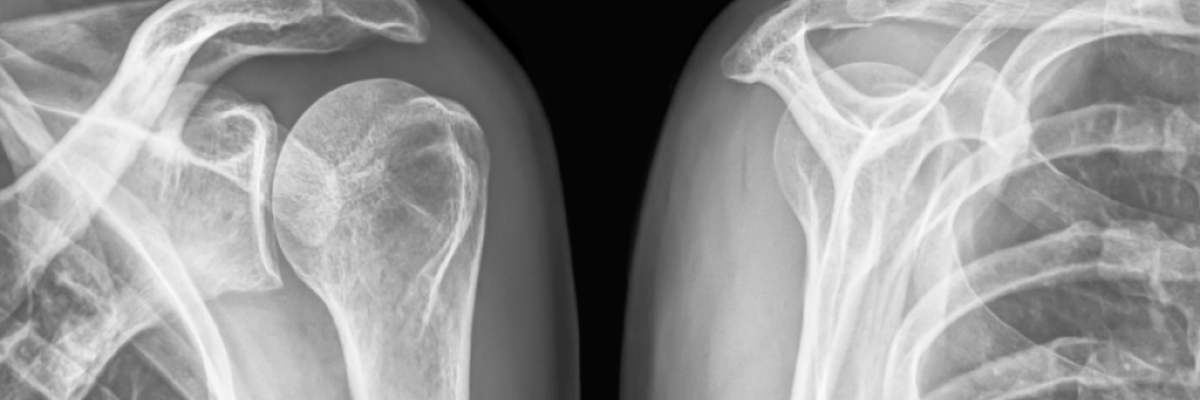

El síndrome subacromial ocurre cuando hay una reducción del espacio entre el acromion (hueso del omóplato) y los tendones del manguito rotador, lo que genera fricción al mover el hombro. Puede causar: